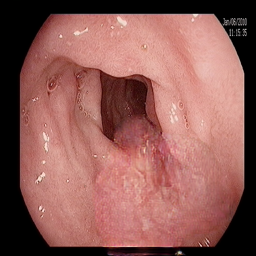

At this stage of the experiments, the generated polyps from PolypConnect (using the EdgeConnect model as the main inpainting model) are prepared for the segmentation evaluation. In total, there are four datasets. Therefore, we train four U-Net [27] models for segmentation. The baseline dataset consists of only real polyp images. The remaining are datasets combining the real and generated polyp images. The first combined dataset consists of 800800800 real and 800800800 generated. The second and third are similar but with 160016001600 and 240024002400 generated polyp images. The models were evaluated on the same validation set of 200200200 real images. The obtained metrics show a clear improvement in all models trained on the additional synthetic data. Results can be found in Table III.

Refer to caption Refer to caption Refer to caption Refer to caption Refer to caption Refer to caption

(a) (b) (c) (d) (e) (f)

Figure 4: Visual comparison of segmentation performance with UNet architecture when synthetic data is used. (a) Input Image. (b) Ground Truth. (c) Baseline (UNet) only with 800 real data (d) real data +800 (e) real data + 1600 (f) real data + 2400.